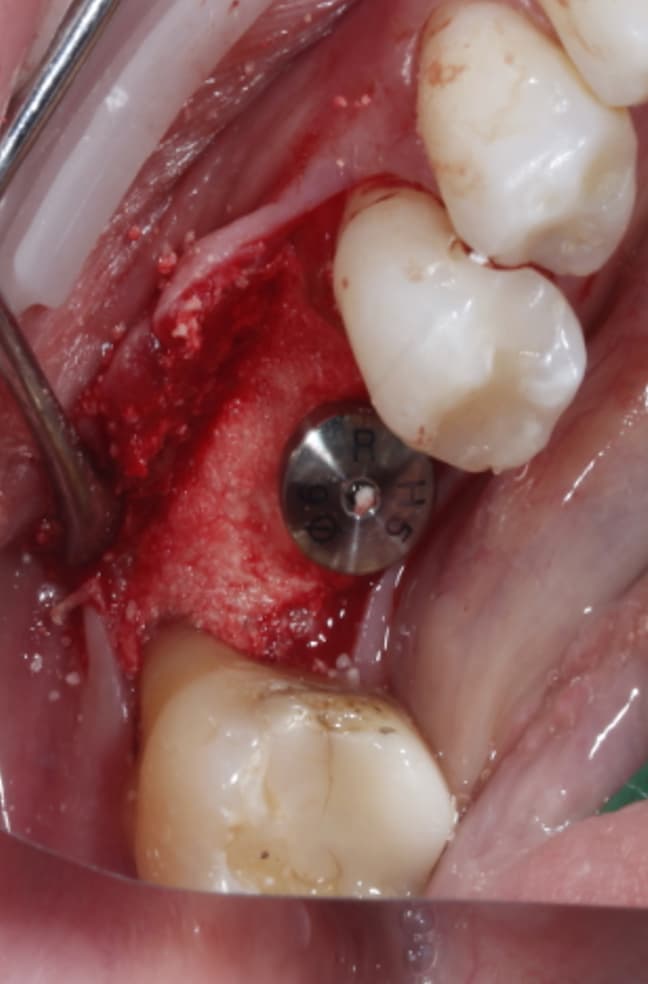

Buccal bone missing after implant placement

(preoperative picture for LL6), LL6 was extracted about 10 weeks before implant placement

( after 3 months, implant was uncovered but the buccal cervical bone is missing , there is no denture use at all and the buccal wall just disappeared. there was no bone graft or membrane used when the implant was placed)

at the end, Ethoss, beta-TCP was grafted and moulded around the implant to close again.